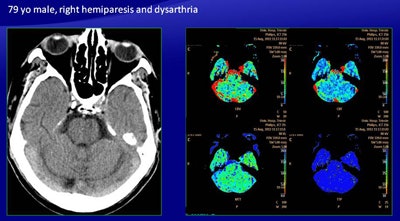

Among the ischemic penumbra results, one true positive on CBV analysis was a false negative on the automatically generated map, representing a large ischemic penumbra of the parietal lobe, adjacent to a large stroke.

For infarcted tissue, in four of 14 cases there was a discordance -- all true positive on the manually generated maps and all false positive on the software generated maps. These included three false positives in the basal ganglia. There was also one false negative produced by the software.

"There was an area of reduced CBV, reduced CBF, and increased MTT in the left pons, suggesting an infarction of the pons, but the color map showed only abnormalities, leading to a false negative revealed in the follow-up CT, which showed a large infarct in the pons," Ukmar said.